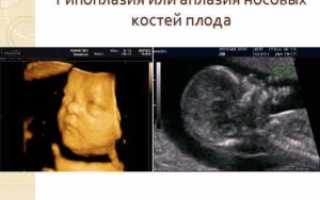

Длина кости носа является показателем определения нормального развития плода. Выделяют два патологических состояния – гипоплазия и аплазия. Гипоплазия — это уменьшение ее длины, а аплазия – это отсутствие данной кости.

Если видно, что показатели маленькие, т.е. имеются отклонения в сторону уменьшения, то это состояние является признаком гипоплазии. Явной патологией и отклонением является отсутствие косточек, что указывает на абсолютное недоразвитие этого органа и грубую аномалию. Это происходит редко, в исключительных случаях.

Носовые кости — это четырехугольные удлиненные косточки, которые просматриваются уже на 10–11 неделе беременности. Если длина носовой кости у плода оказываются меньше, чем должна быть на данном сроке беременности, то в этом случае говорят о гипоплазии носовой кости. Если носовая кость у плода полностью отсутствует, то это состояние называется аплазией.

Длина кости носа у эмбриона – один из важнейших показателей правильного развития плода. Если носовая кость на УЗИ имеет размер меньше нормы, можно говорить о таком явлении, как гипоплазия носовой кости у плода.